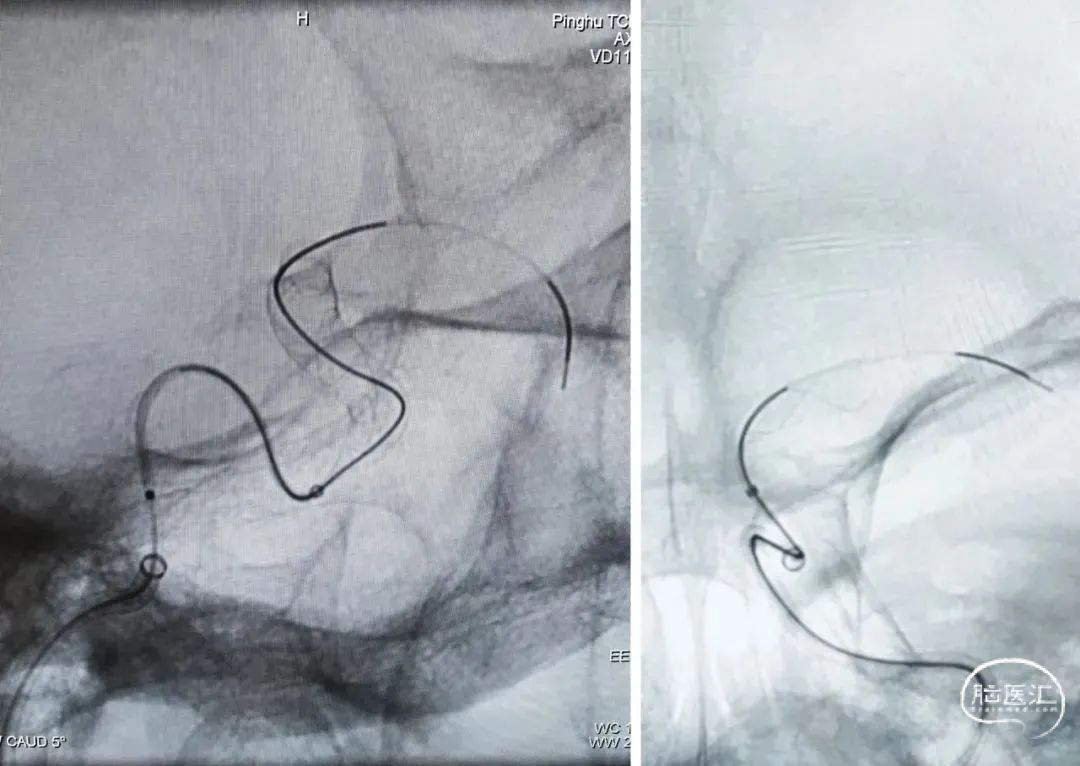

泰杰Frepass® TJMC18Plus支架微导管、6F 中间导管同轴上高,微导丝引导泰杰Frepass® TJMC18Plus支架微导管顺利上高至大脑中动脉M1平直段。微导丝引导栓塞微导管顺利进入瘤内。

输送Nuva®血流导向密网支架 TJED-D-5.5-20顺利到位,释放头端及定位支架远端。

继续释放Nuva®血流导向密网支架。

密网支架半释放状态下,沿栓塞微导管顺利填入泰杰Perfiller®栓塞用可膨胀弹簧圈系统 9mm*30cm ,然后撤出栓塞微导管。

完全释放支架后即刻造影,可见支架贴壁良好。